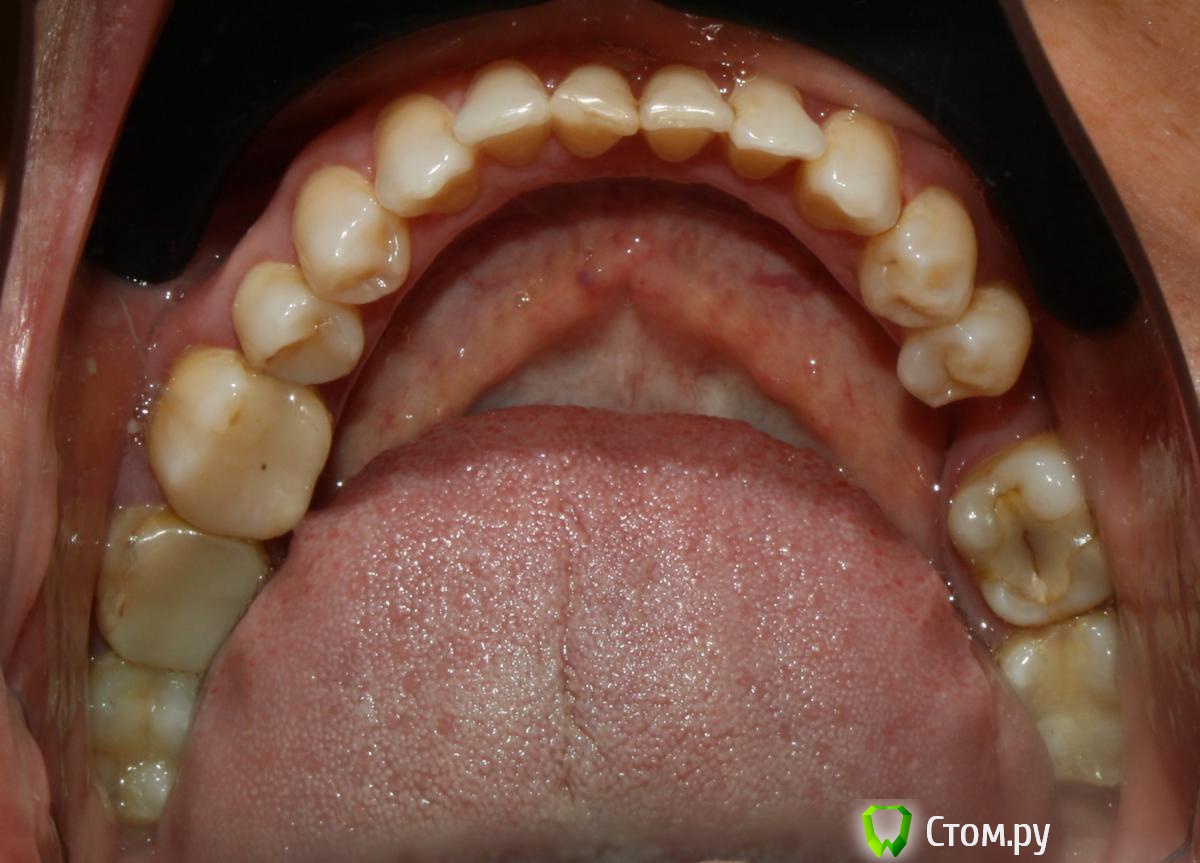

artem29 Опубликовано 12 декабря, 2013 Поделиться Опубликовано 12 декабря, 2013 всем привет!!! Я хирург. В клинике планируется работа с микровинтами. Пациентка брекетсистему "носить" не планирует (остановились на локальном решении задач) Задача: Ортопеду необходимо освободить место для будущих искусственных зубов 1.6 и 3.6. Для этого пациентка (50 лет), отправляется на консультацию к ортодонту для решения вопроса у дистализации зубов 1.7 и 3.7. В данном клиническом случае по хирургическим показаниям зубы мудрости планировались на удаление, сейчас добавились и ортодонтические, как я понимаю для дистализации 1.7 и 3.7 надо удалить 1.8 и 3.8. Ортодонт на микровинтах не работала, но мотивация есть. С ортодонтом видемся редко, у нас в клинике только консультативны прием, обсудить что-то вместе крайне редко получается (тем более провести совместную консультацию), меня как хирурга ортопед попросил посмотреть снимки, определить свой (хирургический объем работы). Изучив информацию (литературу и форумы) я пришел к такому варианту действий,чтобы дистализировать 1.7 необходимо удалить 1.8 установить микровинт вестибулярно между корнями 1.4 и 1.3 (т.к. там больше места чем между 1.5 и 1.4) к 1.7 фиксировать брекет-замок, между ними установить пружину, зуб 1.7 дистализируется. для дистализации 3.7 необходимо удалить 3.8, оценить состояние костной ткани, возможно установить микровинт дистально одномоментно с удалением 3.8 если межокклюзионной высоты для головки микровинта будет достаточно. Вторым путем (при отсутствии состоятельной костной опоры в момент удаления 3.8 является установка микровинта между корнями зубов 3.4 и 3.5, брекет на зуба 3.7 + пружина. есть ещё один вариант. удалить 1.8 и 3.8, дождаться пока пройдет формирование костной ткани (сделать КТ через 3 месяца) установить микровинты в уже сформированную кость Вопросы: 1. кто определяет место установки микровинтов, ортодонт или хирург? 2. если изначально определяет место установки винтов хирург, то какие зоны необходимо в данной случае взять за костные опоры (куда ставить установить микровинты) к какие ортодонтические конструкции будут? 3. оптимально ли в данной ситуации дистализировать с помощью микровинтов, или возможны другие варианты Ссылка на комментарий

M@estro Опубликовано 12 декабря, 2013 Поделиться Опубликовано 12 декабря, 2013 Интрузию 4.6 и 2.6 я просить бы не стал. (а 2.6 вообще под вопросом на выход). Думаю, дистализацию в первом квадранте можно выполнить "пружинкой" ,оттолкнувшись от премоляров,хотя утверждать не берусь. P.s. Гигиена - кошмар. Ссылка на комментарий

Ayrat_zub Опубликовано 12 декабря, 2013 Поделиться Опубликовано 12 декабря, 2013 (изменено) конкретно всем привет!!! Я хирург. В клинике планируется работа с микровинтами. Пациентка брекетсистему "носить" не планирует (остановились на локальном решении задач) Задача: Ортопеду необходимо освободить место для будущих искусственных зубов 1.6 и 3.6. Для этого пациентка (50 лет), отправляется на консультацию к ортодонту для решения вопроса у дистализации зубов 1.7 и 3.7. В данном клиническом случае по хирургическим показаниям зубы мудрости планировались на удаление, сейчас добавились и ортодонтические, как я понимаю для дистализации 1.7 и 3.7 надо удалить 1.8 и 3.8. Ортодонт на микровинтах не работала, но мотивация есть. С ортодонтом видемся редко, у нас в клинике только консультативны прием, обсудить что-то вместе крайне редко получается (тем более провести совместную консультацию), меня как хирурга ортопед попросил посмотреть снимки, определить свой (хирургический объем работы). Изучив информацию (литературу и форумы) я пришел к такому варианту действий,чтобы дистализировать 1.7 необходимо удалить 1.8 установить микровинт вестибулярно между корнями 1.4 и 1.3 (т.к. там больше места чем между 1.5 и 1.4) к 1.7 фиксировать брекет-замок, между ними установить пружину, зуб 1.7 дистализируется. для дистализации 3.7 необходимо удалить 3.8, оценить состояние костной ткани, возможно установить микровинт дистально одномоментно с удалением 3.8 если межокклюзионной высоты для головки микровинта будет достаточно. Вторым путем (при отсутствии состоятельной костной опоры в момент удаления 3.8 является установка микровинта между корнями зубов 3.4 и 3.5, брекет на зуба 3.7 + пружина. есть ещё один вариант. удалить 1.8 и 3.8, дождаться пока пройдет формирование костной ткани (сделать КТ через 3 месяца) установить микровинты в уже сформированную кость Вопросы: 1. кто определяет место установки микровинтов, ортодонт или хирург? 2. если изначально определяет место установки винтов хирург, то какие зоны необходимо в данной случае взять за костные опоры (куда ставить установить микровинты) к какие ортодонтические конструкции будут? 3. оптимально ли в данной ситуации дистализировать с помощью микровинтов, или возможны другие вариантыконкретно в этом случае можно обойтись без миниимплантов, имхо) с помощью кантилеверов(специальных пружинок)в первом квадрате- тоже мезиальный наклон моляров насколько вижу всего лишь, тоже провести апрайт, и освободится место) по моделям проще просчитать) положение минимплантов- компромисс между желанием ортодонта, и возможностями хирурга) Изменено 12 декабря, 2013 пользователем Ayrat_zub Ссылка на комментарий